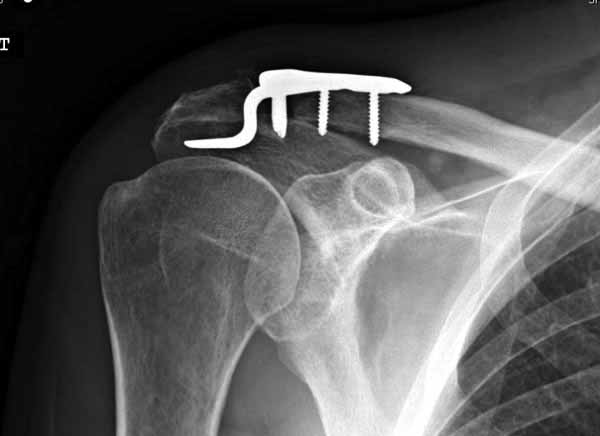

Вложение не в текстовом формате было извлечено…

Имя     : 2 Clavicle AC introp 1.jpg

Тип     : image/jpg

Размер  : 17058 байтов

Описание: отсутствует

Url     : http://weborto.net:8080/pipermail/ortho/attachments/20110623/6adf8600/attachment-0007.jpg

----------- УМЕДХЭБС ЮБУФШ -----------